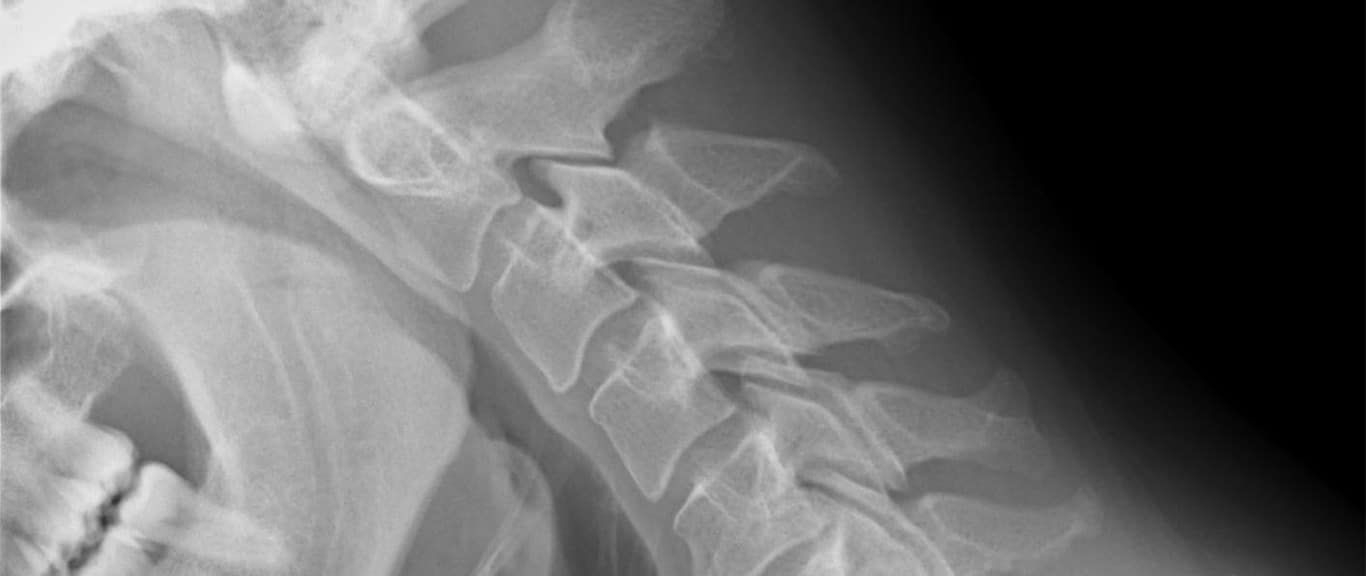

The research has particular potential for the repair of damaged cartilage and bone in joints and the spine – conditions that plague professional athletes and those who do a lot of manual labour as part of their jobs.